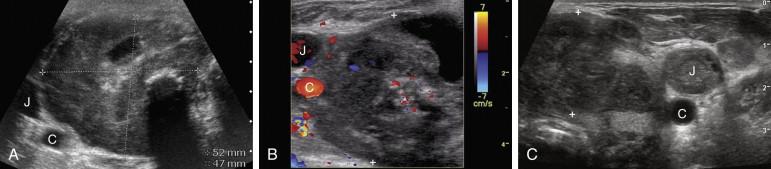

Anaplastic cancer accounts for less than 5% of thyroid malignancies. It is most often seen in patients over the age of 60 and it has a dismal prognosis (5-year mortality rate > 95%). It usually appears as a large, solid, hypoechoic mass ( Fig. 10-14 ). Cystic changes and dense coarse calcifications may be present but microcalcifications are not a feature of anaplastic cancer. Local invasion of adjacent structures is common at the time of presentation.

F igure 10-14, Anaplastic cancer (cursors) in different patients. A, Transverse view shows a large, solid, hypoechoic mass with a cystic area and shadowing calcification. The entire right lobe of the thyroid is replaced and the common carotid artery (C) and the internal jugular vein (J) are deviated laterally. B, Transverse view of the right lobe shows a heterogeneous, predominantly solid mass partially encasing the common carotid artery (C) and internal jugular vein (J). C, Transverse view of the left lobe shows a lobulated, solid, hypoechoic mass. There is invasion of the internal jugular vein (J). The common carotid artery is also seen (C).